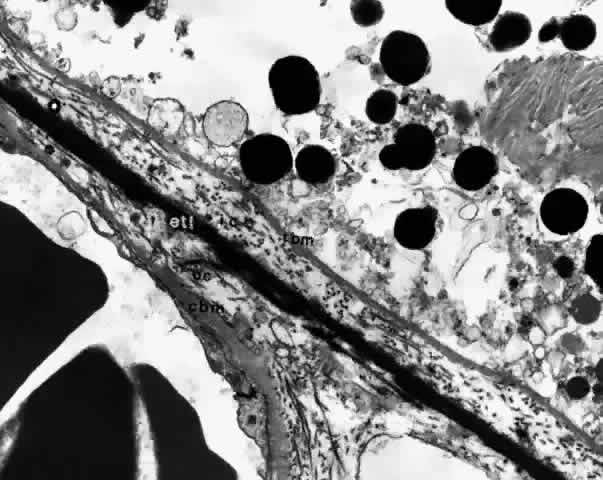

BRUCH'S MEMBRANE

Bruch's membrane, also called the lamina vitrea, is the inner layer of the choroid. This thin, acellular, well-delineated zone between the retina and choroid extends from the optic nerve to the ora serrata. Composed of elements from both the retina and the choroid, Bruch's membrane is an integral part of the choroid. From internal to external, the membrane is formed of five layers: the basement membrane of the RPE, the inner collagenous zone, the elastic tissue layer, the outer collagenous zone, and the basement membrane of the choriocapillaris (Fig. 8).

Fig. 8. Bruch's membrane. Basement membrane of retinal pigment epithelium (rbm), inner collagenous zone (ic), elastic tissue layer (etl), outer collagenous zone (oc) and basement membrane of choriocapillaris (cbm). (× 14,500)

Bruch's membrane is thickest near the optic disc, measuring 2 to 4 μm, and gradually decreases in thickness to 1 to 2 μm peripherally.16 The innermost layer, the basement membrane of the RPE, is a continuous membrane measuring 0.3 μm thick. The outer layer, the basement membrane of the choriocapillaris, is 0.14 μm thick and is discontinuous at the intercapillary septa. The inner and outer collagenous layers are continuous and measure 1.5 μm and 0.14 μm, respectively. The middle elastic tissue layer is discontinuous. Normally, the layers of Bruch's membrane are so closely interwoven that they cannot be separated in a healthy globe.17–20

Ultrastructurally, the basement membrane of the RPE and choriocapillaris is made of fine filaments that blend with the collagen of the adjacent collagenous zones. The basement membrane of the RPE is separated from the cytoplasmic membrane of the RPE, from which it is derived, by a 100 nm radiolucent zone. The cytoplasmic membrane of the RPE cell has many infoldings, which its basement membrane usually does not follow, although it may project slightly into the outer part of some folds.22,23 The basement membrane of the RPE is continuous with the basement membranes of the pigmented epithelium of the ciliary body and anterior pigmented epithelium of the iris and, therefore, extends from the optic disc to the pupillary edge of the iris. The basement membrane of the choriocapillaris is discontinuous at the intercapillary septa.

The inner and outer collagenous zones are made up of randomly oriented collagen fibers measuring 60 nm in diameter. Many are parallel to the retina, and others pass from the inner collagenous zone through the elastic layer into the outer collagenous zone. At the ora serrata, the inner collagenous layer thickens, displacing the elastic layer outwardly.

The elastic layer, the middle layer of Bruch's membrane, is a dense, irregularly interrupted band composed of interwoven elastic tissue fibers of various thickness. The elastic fibers are ultrastructurally composed of long and straight rods with a homogeneous core and dense cortex. Variably sized spaces are present between the elastic fibers. They provide passageways for collagen fibers from the inner collagenous zone to the outer collagenous zone and into the intercapillary septa and subcapillary zone of the choriocapillaris (Fig. 10). The elastic tissue and collagenous layers of Bruch's membrane become circularly oriented around the edge of the optic nerve.